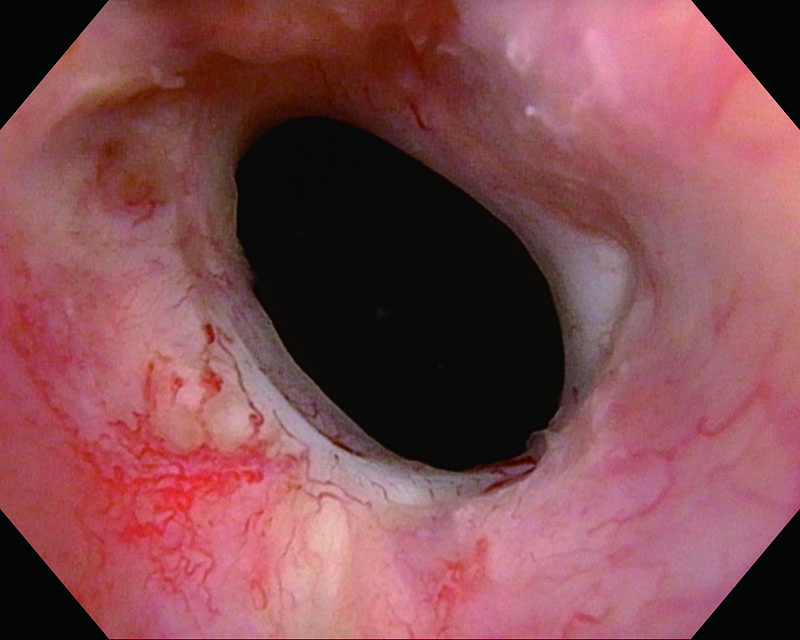

Congestive mucosa of the bladder's trigone, age 28, female

White Light

NBI™ Technology

Congestive mucosa of the bladder trigone. NBI™ Technology enhances the hyper vascularized area. Histology showed pTa, Low grade (G2).